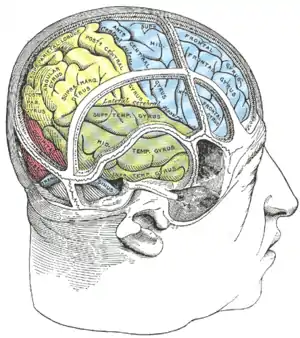

Lobes of the human brain (the occipital lobe is shown in red) | |

Drawing to illustrate the relations of the brain to the skull. Occipital lobe in blue

Occipital lobe in blue Occipital lobe